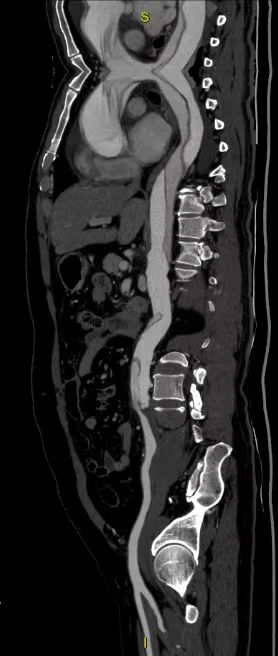

患者48岁,四天前晚上7点突发胸部扯破样痛苦并伴有大汗,因无法忍耐而就诊于本地县病院,初步诊断急性心梗而行冠脉造影,究竟却发现是要命的急性A型自动脉夹层,眷属第一个回响:去北京!

焦炙的眷属四处探询,得知亲戚的同伙也曾患这个病,而且在唐山中心病院心脏大血管外科手术获得治愈的,于是决意转到唐山中心病院进行救治。患者于凌晨3:00点入院,立即进入绿色通道并按急性A型自动脉夹层路径进行处理。值班大夫做了如上介绍。

列入商议的有麻醉科、超声科、手术室、监护室及心脏大血管外科的医护人员,人人就这个病人纷纷揭橥了本身的定见,商议的核心还在手术的时机上,认为自动脉夹层的手术自己出血的风险就大,加之患者口服了两种冲击量的抗凝药物,如今手术出血的风险就更大了。而急性A型自动脉夹层是人类最凶险的疾病之一,在其发病后其灭亡率每小时增加1%,若患者发病48小时内不成急诊手术灭亡率为50%,2周内不手术病死率约75% 。对患者来说,灭亡随时降临。张晶副院长在综合人人的定见后,决意率领团队急诊给患者行手术治疗,“如今手术更能给患者带来生的进展!固然风险较其他夹层手术高”,张晶副院长如是说。 经与眷属充裕沟通,赞成手术!

一切都在心脏大血管外科团队医护人员的手下重要而有序地进行。手术历时9个小时,顺利完成“升自动脉置换+全弓置换+支架象鼻手术”。在医护人员的配合治理下,患者于术后12天顺利出院。全体医护人员都为患者和眷属感应由衷地愉快。